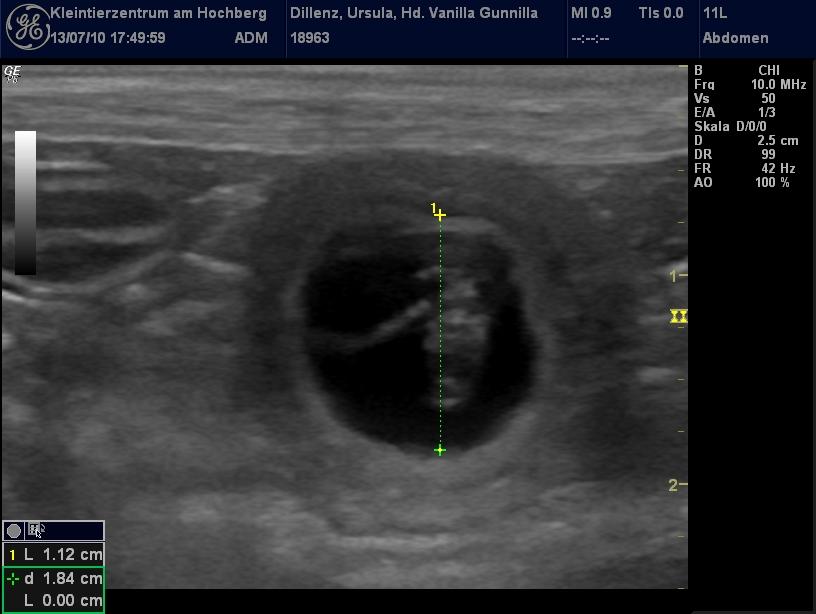

Der Ultraschall hat ergeben, dass unsere Gunni trächtig ist. Wir freuen uns auf unsere H-Wurf-Babys, die um den 20.8.2010 zur Welt kommen werden!